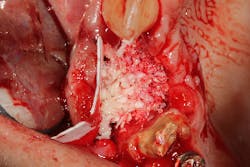

The patient was referred to a periodontist who first augmented the edentulous site with a hard-tissue graft and membrane (figures 8 and 8a). Six months later, implants were placed in ideal positon (figure 9).

At the time of Stage II, six months after implant placement, a palatal roll soft-tissue augmentation was performed (figures 10 and 10a). Six weeks later, the area was provisionalized with new temporaries to develop soft tissue.